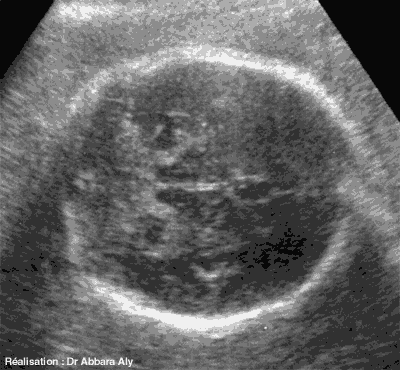

Coupes horizontales occipito-frontales

du cerveau fœtal à 39 SA